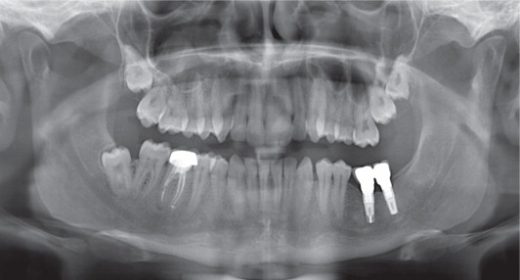

La Parodontologia è un ramo dell’Odontoiatria, che si occupa dello studio delle malattie che riguardano la bocca ed in modo particolare dei denti. Il parodonto è costituito da : gengiva; osso alveolare; cemento radicolare...